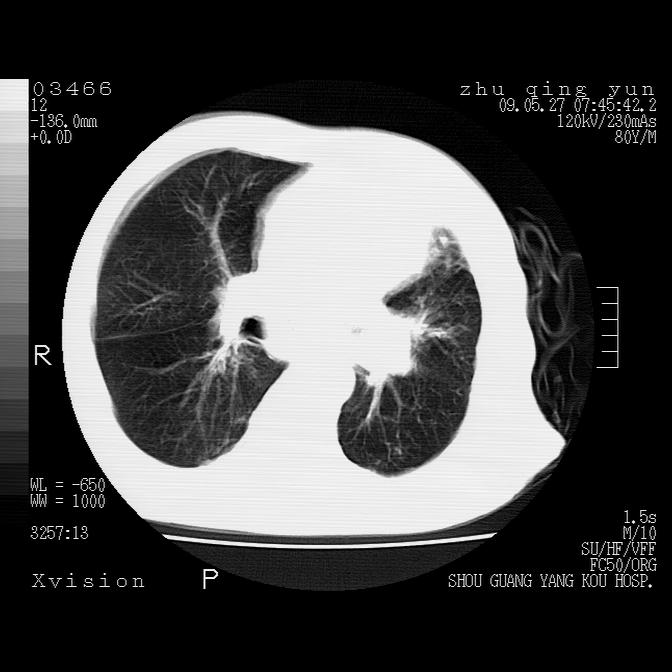

病人男性,年龄80,气喘来院,其他病史不太详细,1月前有过恶心,呕吐,在当地人民医院做过钡餐,诊断胃炎,

1)考虑左肺中央型肺癌并阻塞性肺炎,后下纵隔受侵伴纵隔淋巴结转移。2)双侧少量胸腔积液,胸膜增厚。3)心包积液。

左肺下叶见多发片状及结节状病灶,左肺基底段支气管闭塞,纵隔内见多发淋巴结肿大,纵隔向左侧移位,左侧胸廓变小。应该是左肺下叶中心型肺癌,纵隔淋巴结转移,左侧肺内转移,左肺基底段肺不张,阻塞性肺炎。

1)考虑左肺中央型肺癌并左肺下叶阻塞性肺炎、不张;左胸膜腔积液、心包积液、纵隔淋巴结转移;癌肿累及左心房。2)左心室大。冠状动脉壁钙化斑。